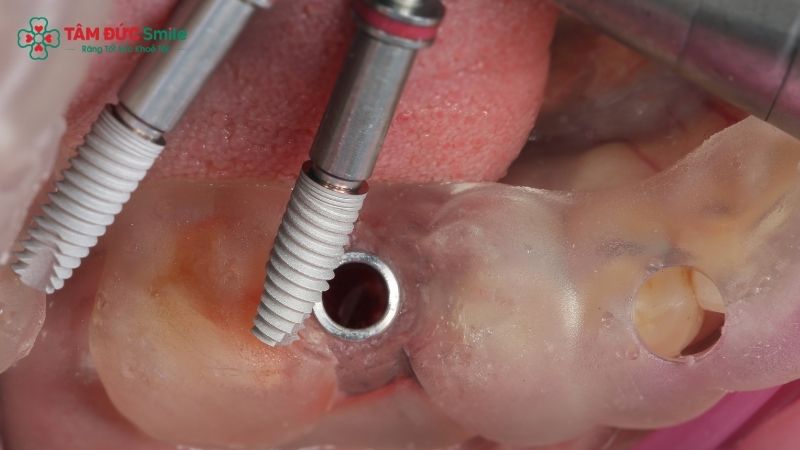

2.5. Surgical placement with guided osteotomy

During surgery, the guide is securely positioned in the mouth. The dentist performs guided osteotomy, drilling through the guide sleeves to prepare the implant site.

This controlled process ensures precise depth and angulation, minimizing human error and protecting surrounding tissues.